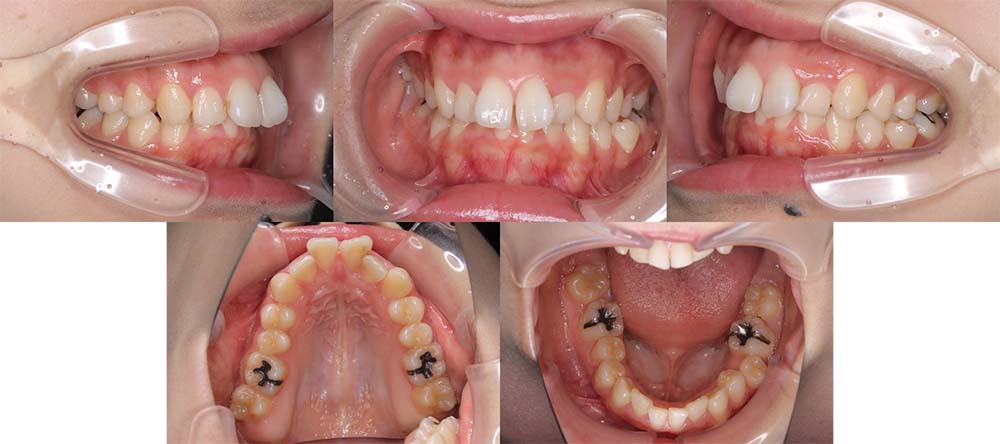

| 症例分類 | 上顎前突、叢生、シザースバイト |

| 診断名 | 右上7のシザーズバイトを伴う上下重度叢生skeletal2 |

| 主訴 | 歯並びが悪くて全体的にガタガタ |

| 年齢 | 19歳11ヶ月 |

| 性別 | 女性 |

| 抜歯部位 | 上顎左右と右下の第一小臼歯、左下の第二小臼歯(4本)、上顎右側第二大臼歯 |

| 使用装置 | 裏側のワイヤー装置 |

| 治療期間 | 2年11ヶ月(5ヶ月程度来院出来ない期間あり) |

| 保定装置 | 固定式保定装置、取り外し式保定装置(8時間) |

| 費用 |

[検査・診断料] ¥49,500 [基本施術料] ¥1,331,000 [調整料] ¥5,500/回 [抜歯] ¥5,500/本 [保定装置] ¥55,000(税込) 抜歯や虫歯治療は他院にて費用が別途かかります。(抜歯¥4,000〜10,000/本)

上下の重度叢生と上の歯が前方にあり上顎両側の第一小臼歯と下顎右側第一小臼歯、下顎左側第二小臼歯、上顎右側第二大臼歯(上顎右側親知らずを咬合に使用)を抜去して上下リンガルで治療を行いました。 左上の第二大臼歯部の咬合が深かったため、一時的に頬側に装置をつけさせて頂きました。裏側に装置を装着すると噛み合わせを浅くするためのバイトアップがかなりの量が必要になり咬みづらくなってしまうためです。

5ヶ月程度来院が出来なかった期間がありましたが、問題なく治療を終了することができました。